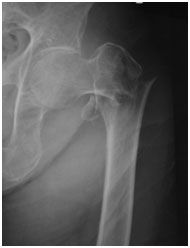

大腿骨頚部骨折 は、全国で年間17万人以上発生しており、高齢化に伴い今後10~20年で年間25万人以上に増加すると予測されています。当院でも手術件数の多い疾患の一つです。大腿骨頚部骨折では、痛みにより歩行が困難になることが多く、原則として手術治療を行います。手術の目的は、骨折部を固定することで痛みを軽減し、早期離床・早期リハビリを可能にすることです。

以下に、当院で行った手術例をご紹介します。

A.転子部骨折:ガンマネイル固定